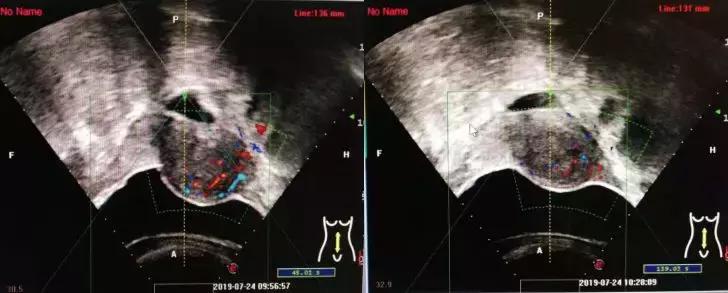

下面四组影像学资料为其中一名子宫肌瘤患者在治疗前、治疗中以及治疗后的影像学表现。

术前超声示血流丰富